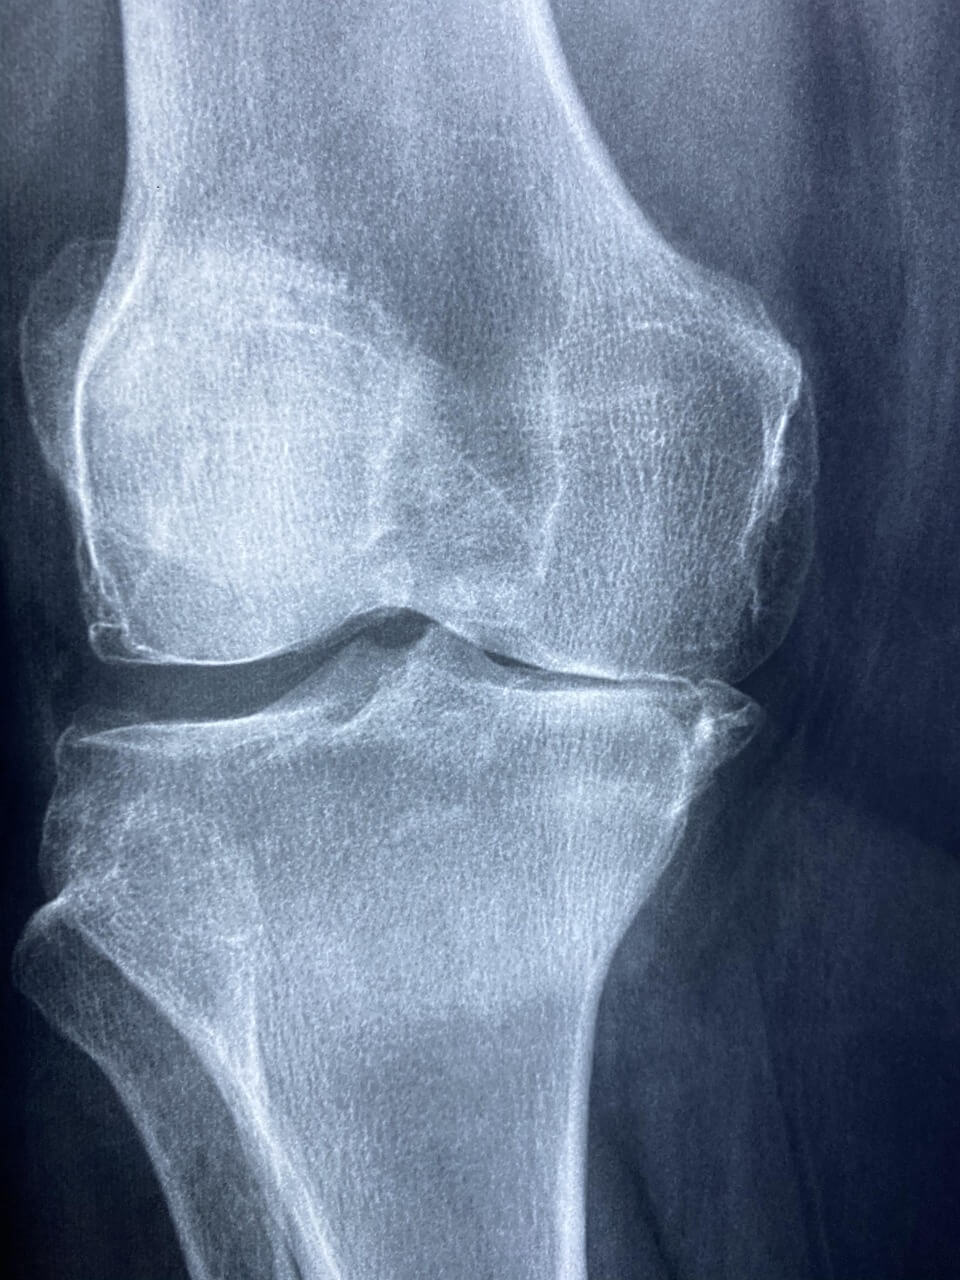

보건복지부는 노인성 퇴행성 관절염으로 인해 무릎 통증을 겪는 고령자를 대상으로 ‘노인 무릎 인공관절 수술 지원사업’을 운영하고 있습니다.

이 사업은 경제적으로 수술이 어려운 저소득층 시니어에게 무릎 인공관절 수술비를 최대 120만 원까지 지원하는 제도입니다.